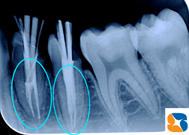

今度は、同じ奥歯を縦割りにした画像です。歯の根の先が、杖のように急カーブをしていたことに再び感動です。

歯の根の治療だけで一日に10人以上の患者様が来られる日も珍しくはありません。CTを使って歯の構造を事前に把握しておけば、よりレベルの高い治療が施術されるはず。16年前に亡くなった歯科医の祖父も「今は凄い時代で羨ましいな〜」と微笑んでいる気がしてなりませんでした。いよいよ歯をCTで診査する時代の到来です。